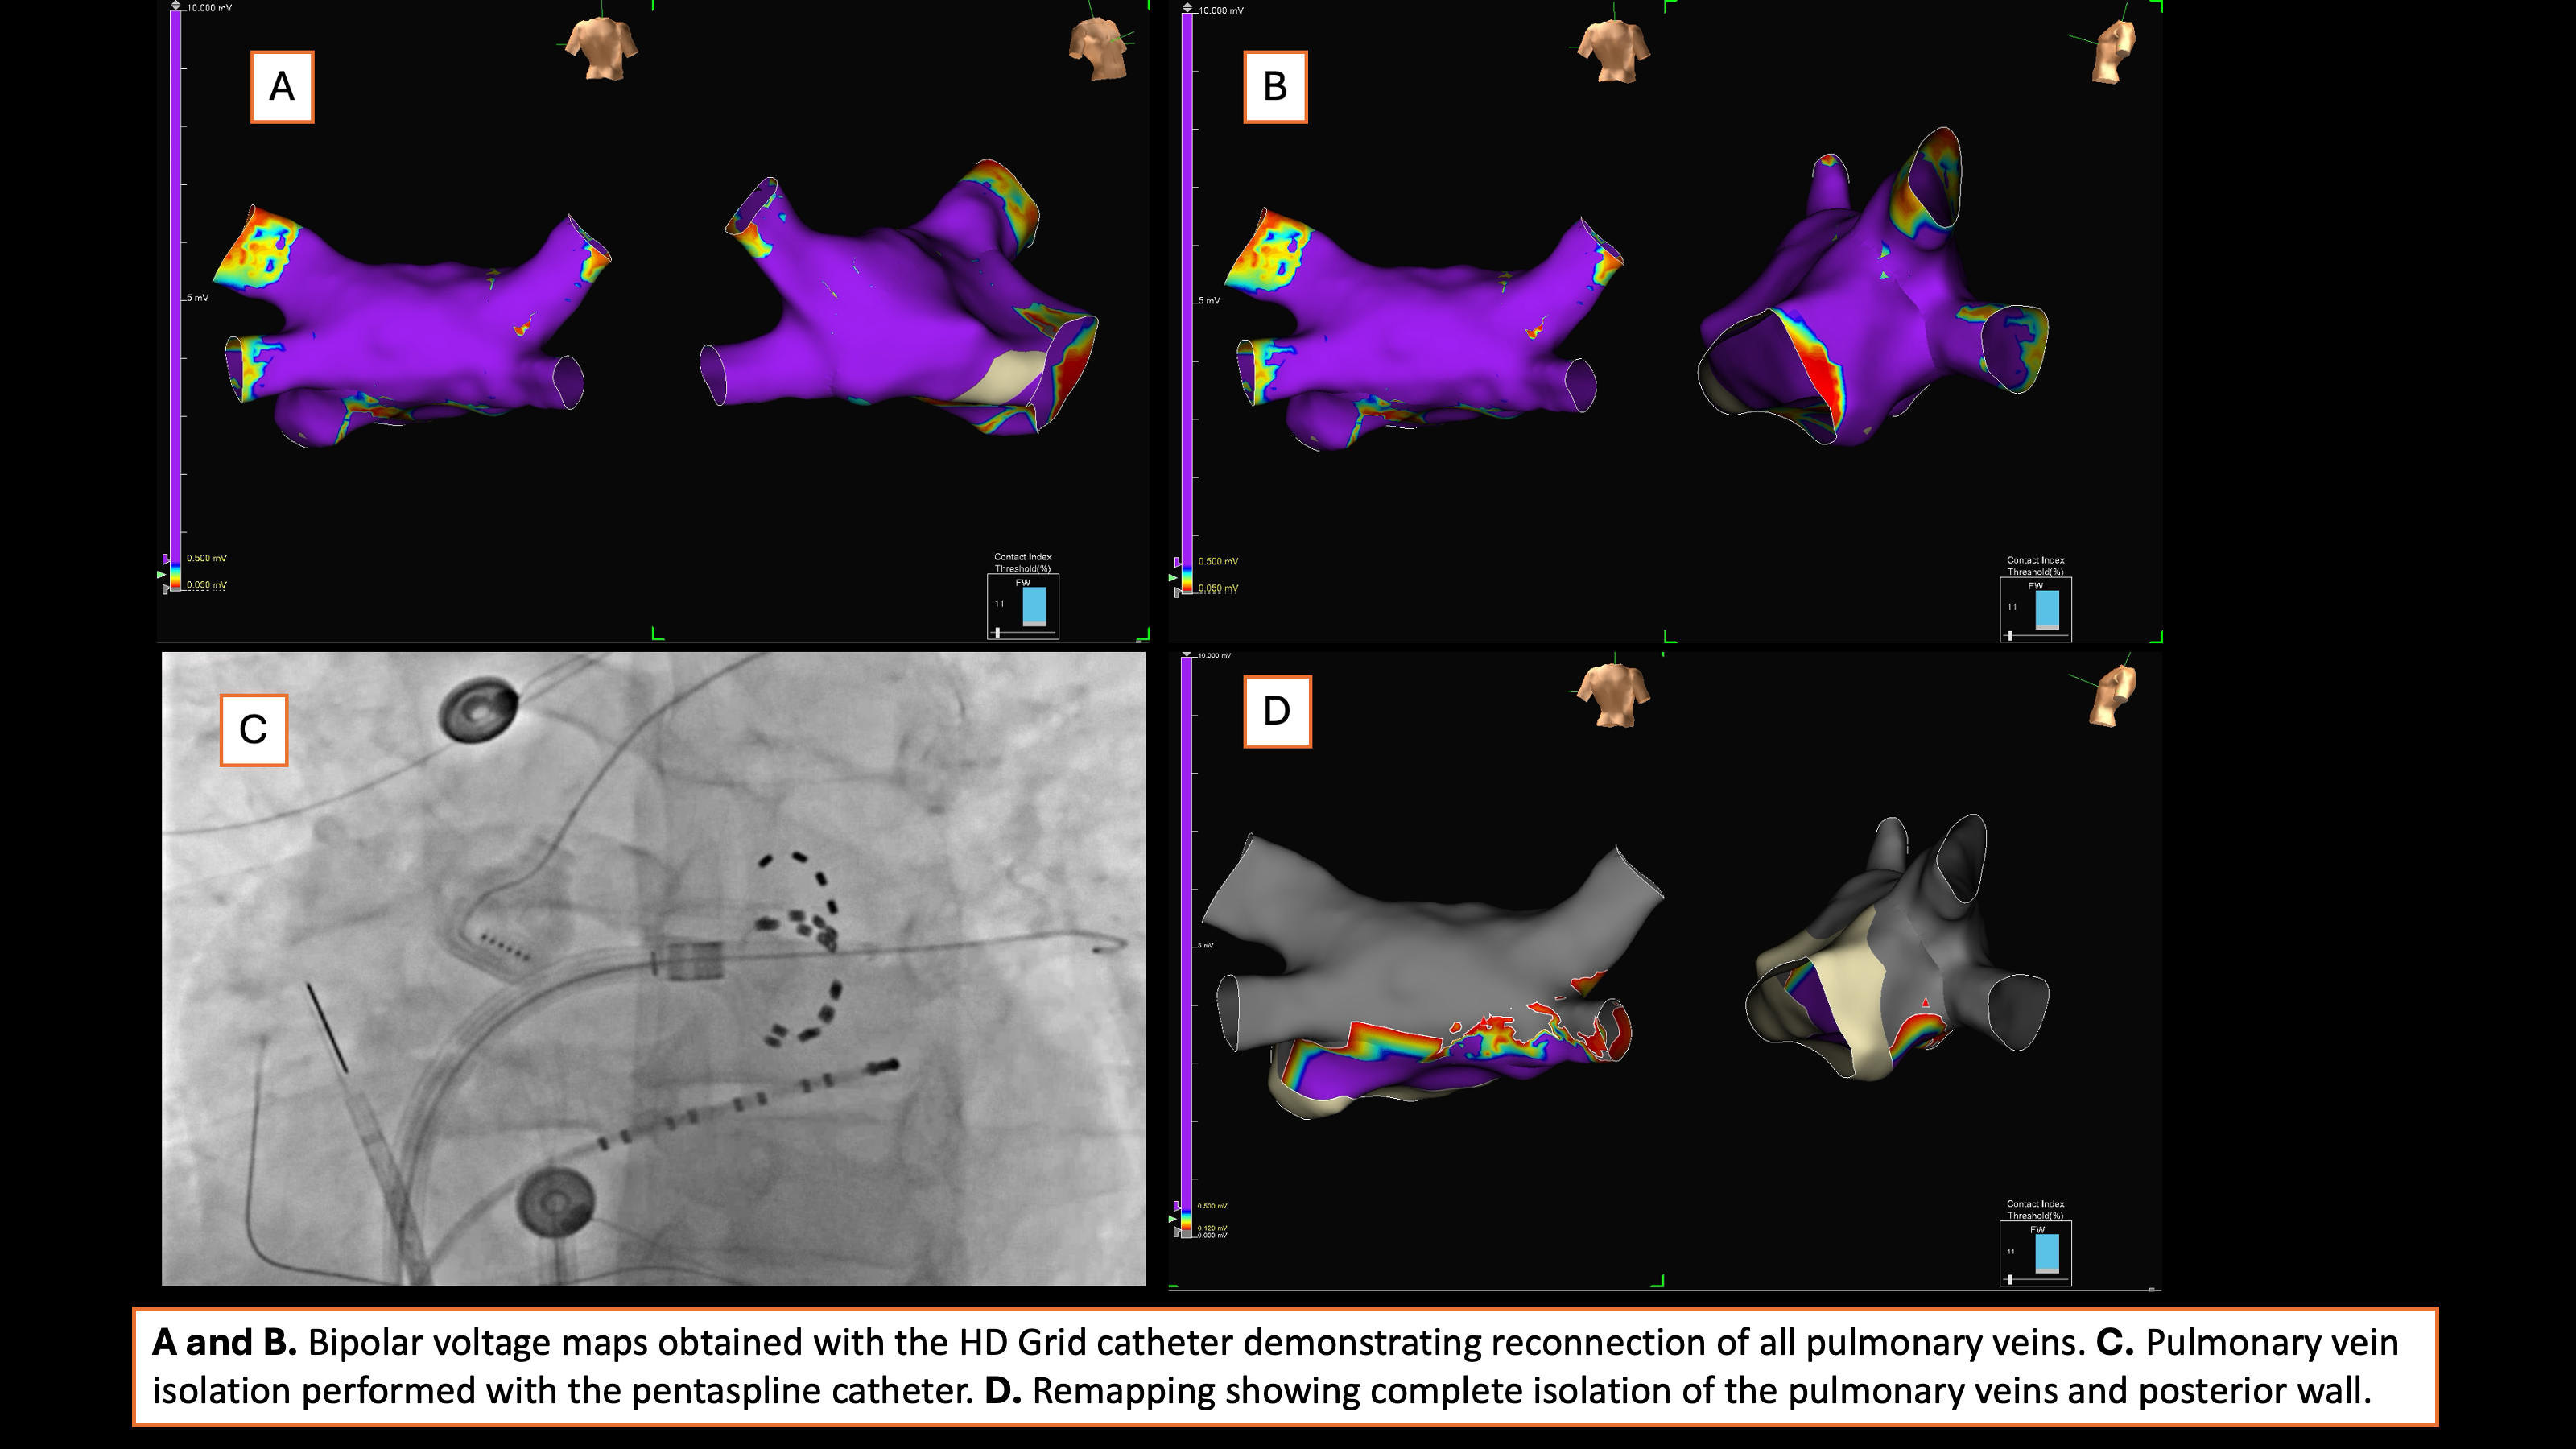

Background: Atrial fibrillation (AF) recurrence remains a significant challenge,...

Background: The addition of posterior wall isolation (PWI) to pulmonary vein iso...

Background: There is limited data on the benefit of posterior wall isolation (PW...